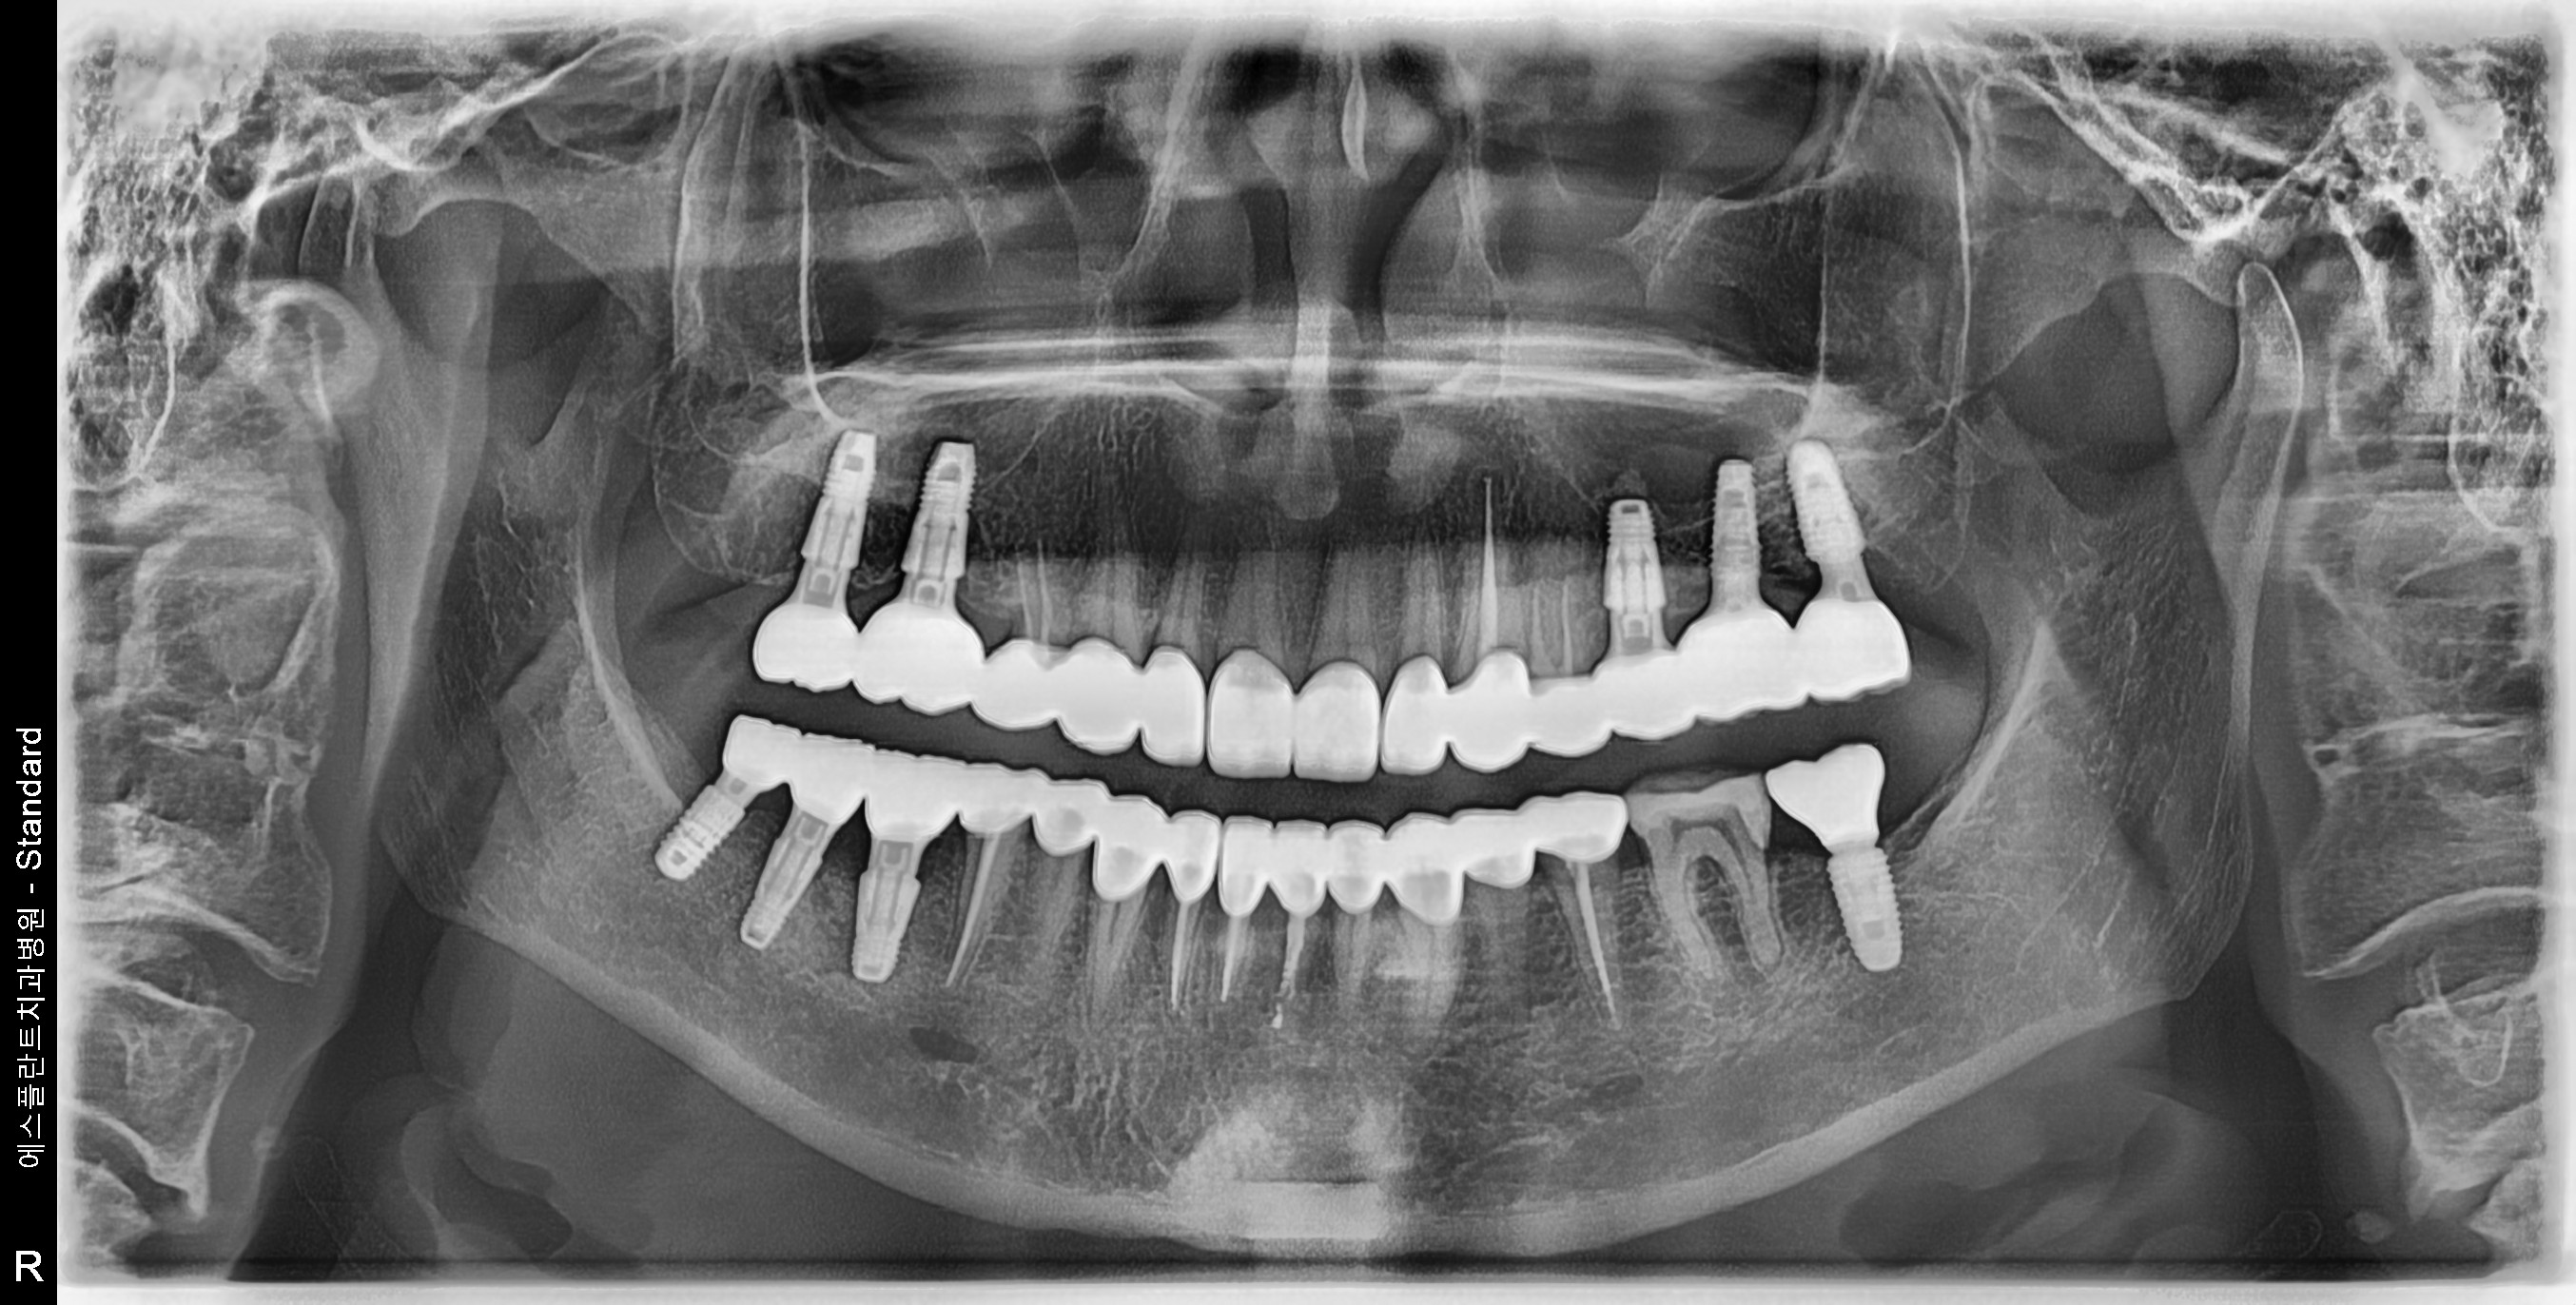

Esthetic prosthetic remake, Dental Implant, Sinus-lifting, Bone Graft

59 y.o, Kazakhstan, Astana

Operating dentist:Roh Hyun Ki